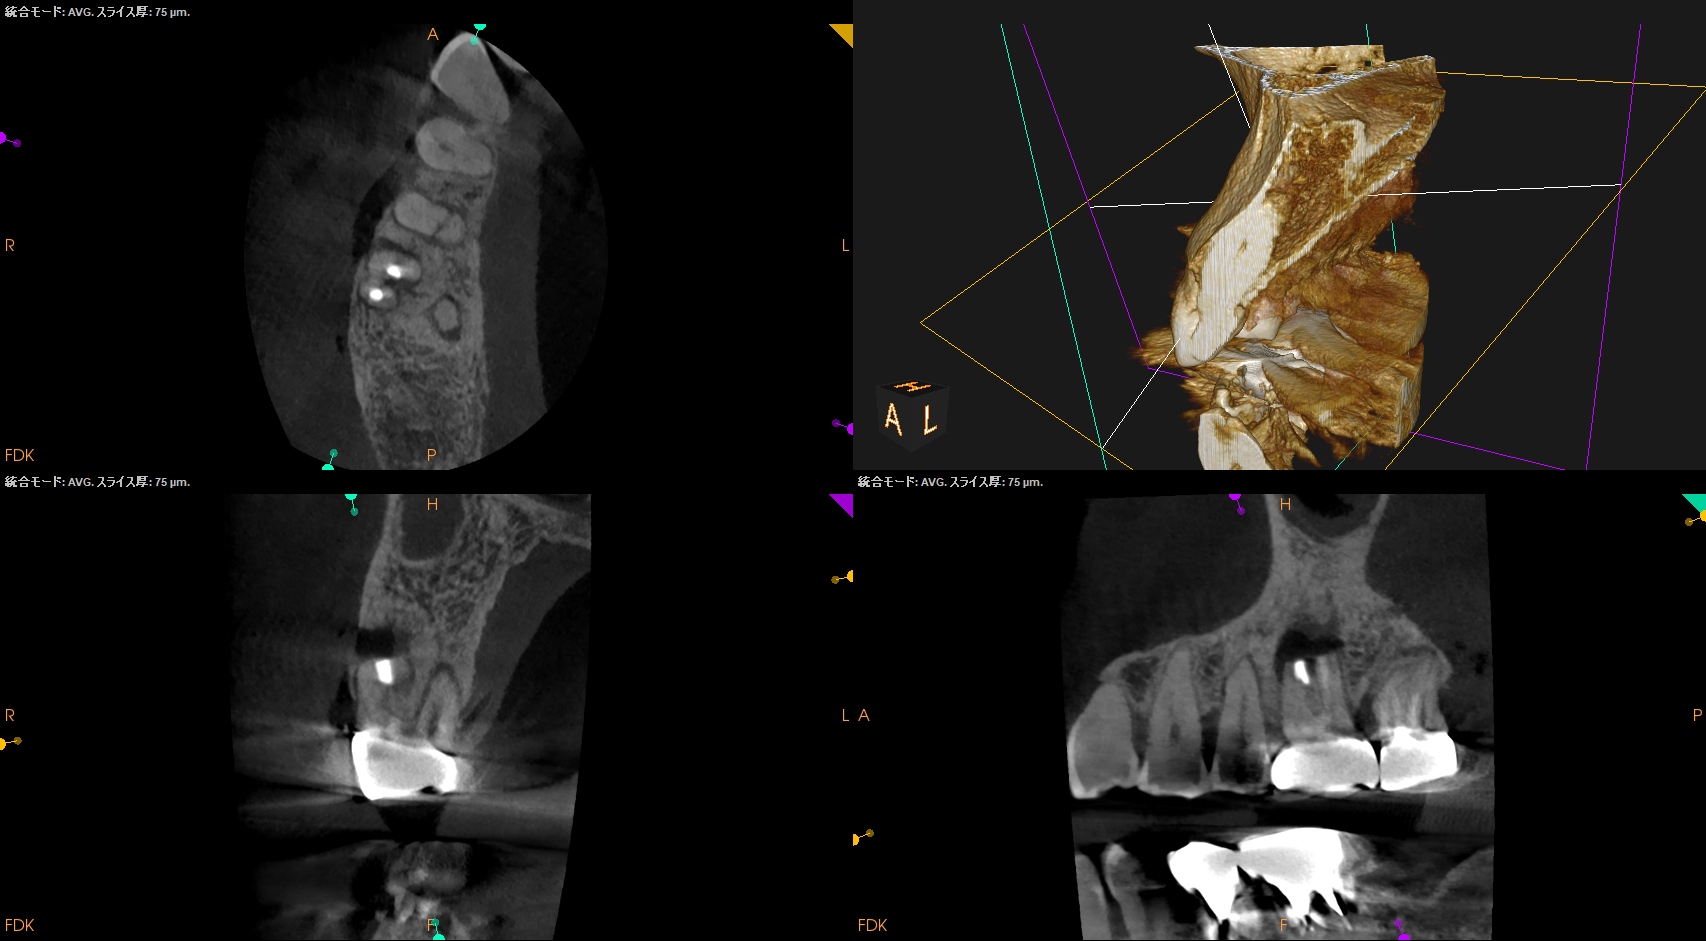

#3 MB,DB Apicoectomy 1yr recall(2025.12.24)

術前のSinus tract・臨床症状(根尖部圧痛)も術後の縫合の傷跡もない。

MB

DB

B

外科治療の際に開創した歯槽骨は再生した。

術前と比較した。

問題は消失した。

MBは根尖部の形成は穿孔しているだろうが即座に穿孔封鎖したから=即座に逆根充したから問題が起きていない。

ということで完治したのでこの日で終診とさせていただいた。